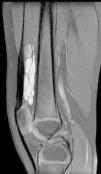

En revisiones posteriores, la paciente se encontraba asintomática entre los episodios de tumefacción articular, con controles de reactantes de fase aguda normales. Se solicitó una resonancia magnética de rodilla derecha, objetivándose una masa sólido-quística en la bursa suprarrotuliana que asociaba imágenes de calcificación sugestivas de flebolitos; se extendía al vastus intermedius y vastus lateralis y medía 83mm de eje mayor craneocaudal, compatible con malformación vascular de bajo flujo tipo venolinfática (figs. 1 y 2).

Se solicitó valoración por cirugía plástica que realizó biopsia incisional de la tumoración en vasto externo que confirmó la presencia de una malformación vascular de predominio venoso. Actualmente sigue revisiones por cirugía plástica y se está realizando esclerosis de la lesión.